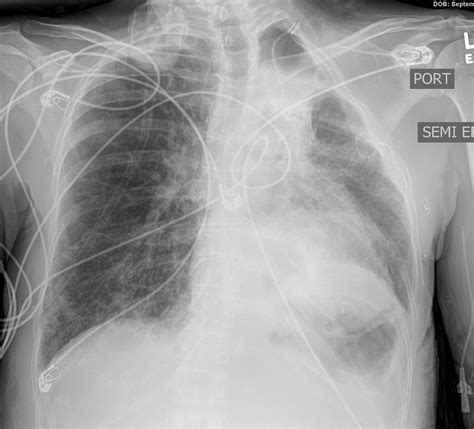

Case Study 1: Pulmonary Edema

A 65-year-old patient presents with shortness of breath and orthopnea. A CXR reveals Kerley B lines in the peripheral lung fields, along with alveolar opacities and pleural effusions. The patient is diagnosed with pulmonary edema secondary to heart failure and is managed with diuretics and oxygen therapy.